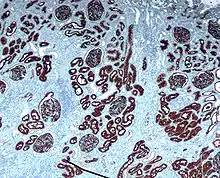

Неприлизин экспрессируется широким спектром тканей, но особенно высокий уровень белка обнаружен в почках. Это частый антиген, обнаруживаемый при остром лимфобластном лейкозе, и является важным маркёром при диагностике заболеваний у человека. Представлен на лейкемических клетках пре-B-лимфоцитарного фенотипа, которые представлены в 85 % всех случаев острого лимфобластного лейкоза[1].